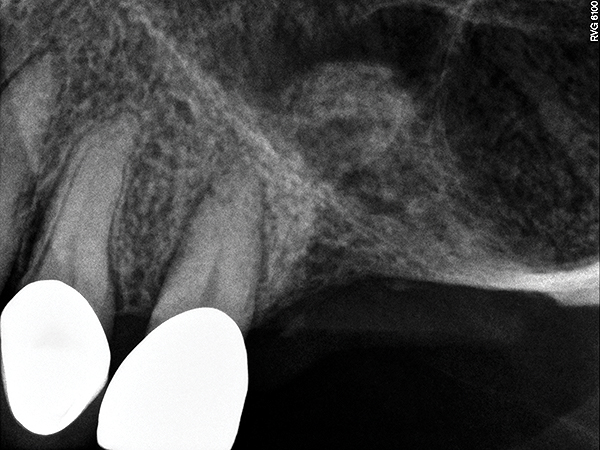

A 74-year-old man presented with only about 2 mm to 3 mm of native bone below the sinus in the No. 14 position (Figure 13). The composite graft used was an approximately 50:50 mixture of DFDBA (Bio-Oss®, Geistlich Biomaterials, www.bio-oss.com) with the addition of about 40% calcium sulfate by volume (Figure 14). The implant placed (Figure 15) was a 10-mm long, rough-surfaced, platform-shifting implant (tapered 4.2 mm to 2.8 mm), and the sinus was raised about 8 mm. The postoperative radiograph taken at 4 months (Figure 16) showed some shrinkage of the graft, but no demarcation of the old sinus floor in the area.

Fig 13. Case 1. Preoperative radiograph showing a ridge height of about 2 mm to 3 mm in the No. 14 position.

Figure 13

Fig 17. Case 2. Preoperative ridge in the No. 14 position. The height of native bone is about 4 mm to 5 mm.

Figure 17

Fig 20. Case 3. Preoperative radiograph showing about 3.5 mm of ridge height.

Figure 20